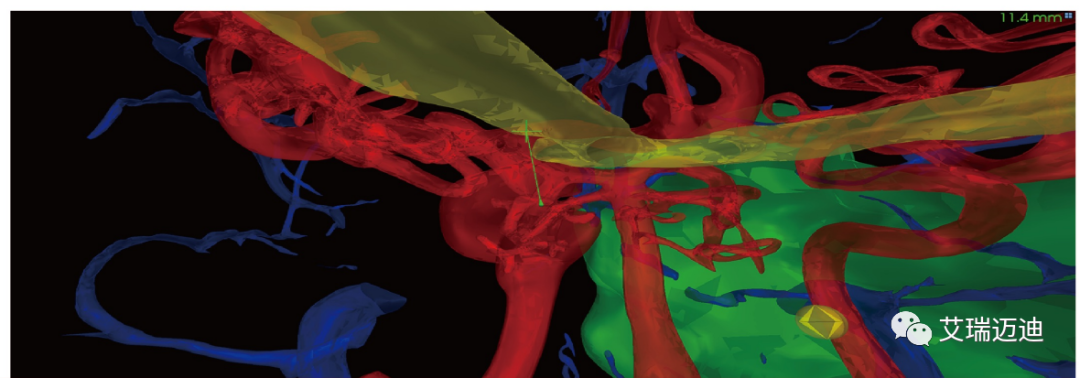

第二,手术安全预警功能。在术中实时计算手术器械与血管神经间真实距离并预警提示,及时提醒医生避开重要组织器官,安全到达手术目标区域。

手术安全预警功能